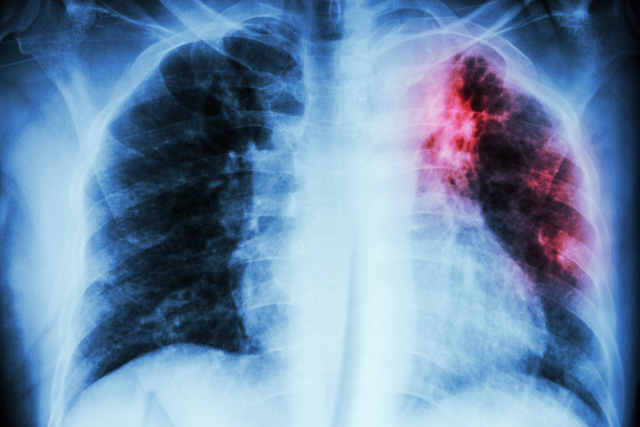

Whitmore là một bệnh truyền nhiễm nguy hiểm, có tỷ lệ tử vong cao và tử vong nhanh nếu bệnh nhân không được chẩn đoán sớm, chẩn đoán đúng và điều trị kháng sinh theo đúng phác đồ khuyến cáo. Đây được cho là bệnh phổ biến ở các nước Đông Nam Á và vùng Bắc Úc. Đặc biệt, Thái Lan, Lào và Campuchia cũng đã công bố nhiều ca bệnh trên các tạp chí y khoa quốc tế.Các yếu tố rủi ro làm tăng nguy cơ mắc bệnh whitmore bao gồm việc đi du lịch đến hoặc sinh sống tại các khu vực dễ phát tán bệnh. Người khỏe mạnh có thể mắc bệnh, tuy nhiên những người vốn mắc những bệnh làm yếu hệ miễn dịch lại càng có nguy cơ mắc bệnh Whitmore cao hơn như bệnh HIV/AIDS, ung thư, bệnh phổi mãn tính, (bao gồm COPD), bệnh gan, bệnh tan máu bẩm sinh, bệnh tiểu đường và bệnh thận mãn tính.Vi khuẩn Whitmore sống ở trong đất và lây nhiễm sang người qua con đường tiếp xúc trực tiếp các vết trầy xước da với đất nhiễm khuẩn. Khi đi vào cơ thể, vi khuẩn có thể tấn công các bộ phận của cơ thể (không loại trừ một bộ phận, một cơ quan cơ thể nào). Dạng phổ biến nhất là tấn công phổi. Bệnh khởi phát sau 1 ngày đến 3 tuần kể từ khi nhiễm bệnh và biểu hiện cấp tính, nhưng 10% ca bệnh có biểu hiện bệnh whitmore mạn tính (trong đó bệnh nhân bị ốm suốt kéo dài trên 2 tháng). Vết loét hoặc áp-xe da, viêm hạch bạch huyết, viêm tuyến mang tai có thể là biểu hiện chính trong một số trường hợp.